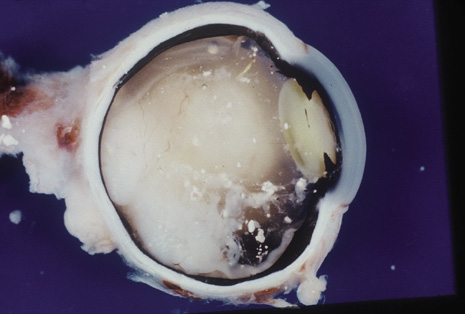

Although keratocentesis had been advocated historically as a treatment for active uveitis, it lost the attention of ophthalmologists until 1919, when Bruckner3 first examined the aqueous humor for diagnostic purposes. Laboratory techniques were revolutionized in the 20th century in areas such as: (a) evaluating very small aliquots of fluid (0.2 to 0.3 mL of aqueous or vitreous), and (b) identifying specific microbial organisms and the predominance of other cell types, antibodies, and proteins in these fluids (Figs. 1, 2, 3, 4, 5, and 6). These advancements have led to the development of diagnostic paracentesis for sight-threatening ocular inflammations that are difficult to diagnose. Witmer4 and O'Connor5 have provided strong evidence that samples of the aqueous humor reflect the antibody-producing capabilities of the iris and ciliary body, particularly when more specific antibody per unit of gamma globulin can be found on the aqueous humor than in the blood of the same patient.6–8 These determinations may be highly significant when one considers the fact that diseased tissue is being bathed in an antibody-containing fluid that is elaborated locally. For instance, in the case shown in Figure 1, the immunofluorescent antibody titer to toxoplasmosis is four times greater in the vitreous aspirate at the time of vitrectomy for repair of retinal detachment than in the plasma. These same considerations have long been recognized in syphilis of the central nervous system, wherein specific antibodies may be present in the cerebrospinal fluid but not in the blood. This is also the case with an unusual presentation of ocular coccidioidomycosis9 or toxocariasis.

Precise identification and culture of bacterial and fungal pathogens from both the aqueous humor and the vitreous fluid can be obtained. Gram's stain and Giemsa's stain smears of centrifuged specimens from the aqueous humor and the vitreous humor frequently demonstrate the bacterial or fungal causative agent. Attempts to isolate bacteria and fungi and to identify them on Gram's stain or Giemsa's stain smears have been most rewarding in the following cases: (a) postoperative endophthalmitis, (b) infection after a penetrating injury of the eye, (c) drug abuse patients with endogenous endophthalmitis (Figs. 21, 22, 23, 24, and 25), (d) patients receiving hyperalimentation, and (4) patients who are immunocompromised as a result of exogenous immunosuppressive agents.

Studies have demonstrated the usefulness of ocular paracentesis for the identification of ocular infections in order to implement sight-saving treatment.10–16 Even acid-fast bacilli and viruses may be diagnosed in this fashion when emergency dictates (see Fig. 5).17 It is recommended that diagnostic paracentesis be performed in all cases of postoperative endophthalmitis, and it is safe to perform the postoperative procedure in the operating room with the safety of vitrectomy surgery. Further, any patient older than 65 who presents with a deteriorating uveitis (usually with vitreitis as the predominant infiltrate) of undetermined etiology should undergo paracentesis of the vitreous to rule out reticulum cell sarcoma (large cell lymphoma).18 Similarly, any patient suspected of being an intravenous drug abuser who presents with an endogenous endophthalmitis or uveitis should undergo diagnostic paracentesis to avoid allowing an intraocular infection to be borne by the bloodstream.19,20